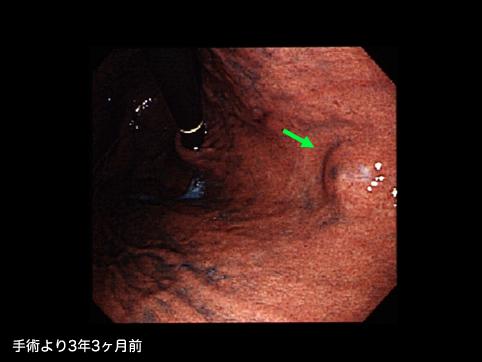

A case of gastrointestinal stromal tumor that extraluminally developed in size during four years and ten months.

악성 비상피성종양/평활근육종

위(부위)/체부

내시경

종양의 최대경(밀리미터)

10~14